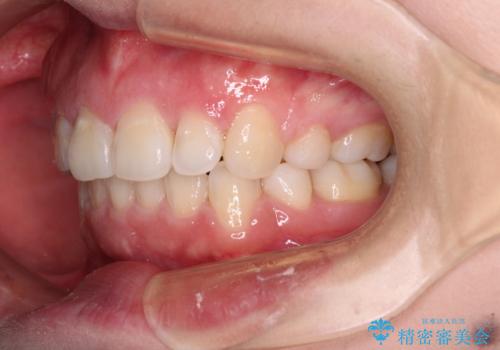

- 前歯のデコボコを気にして来院された患者様です。

当初は口元の突出感はあまり気にされていない様子だったので、インビザラインによる非抜歯矯正をお勧めしたが、ふっくらとした口元を改善したいとのことで、積極的に口元の突出感を改善することとしました。

上下左右第一小臼歯4本の抜歯を行い、ワイヤー装置による矯正治療を行うこととしました。